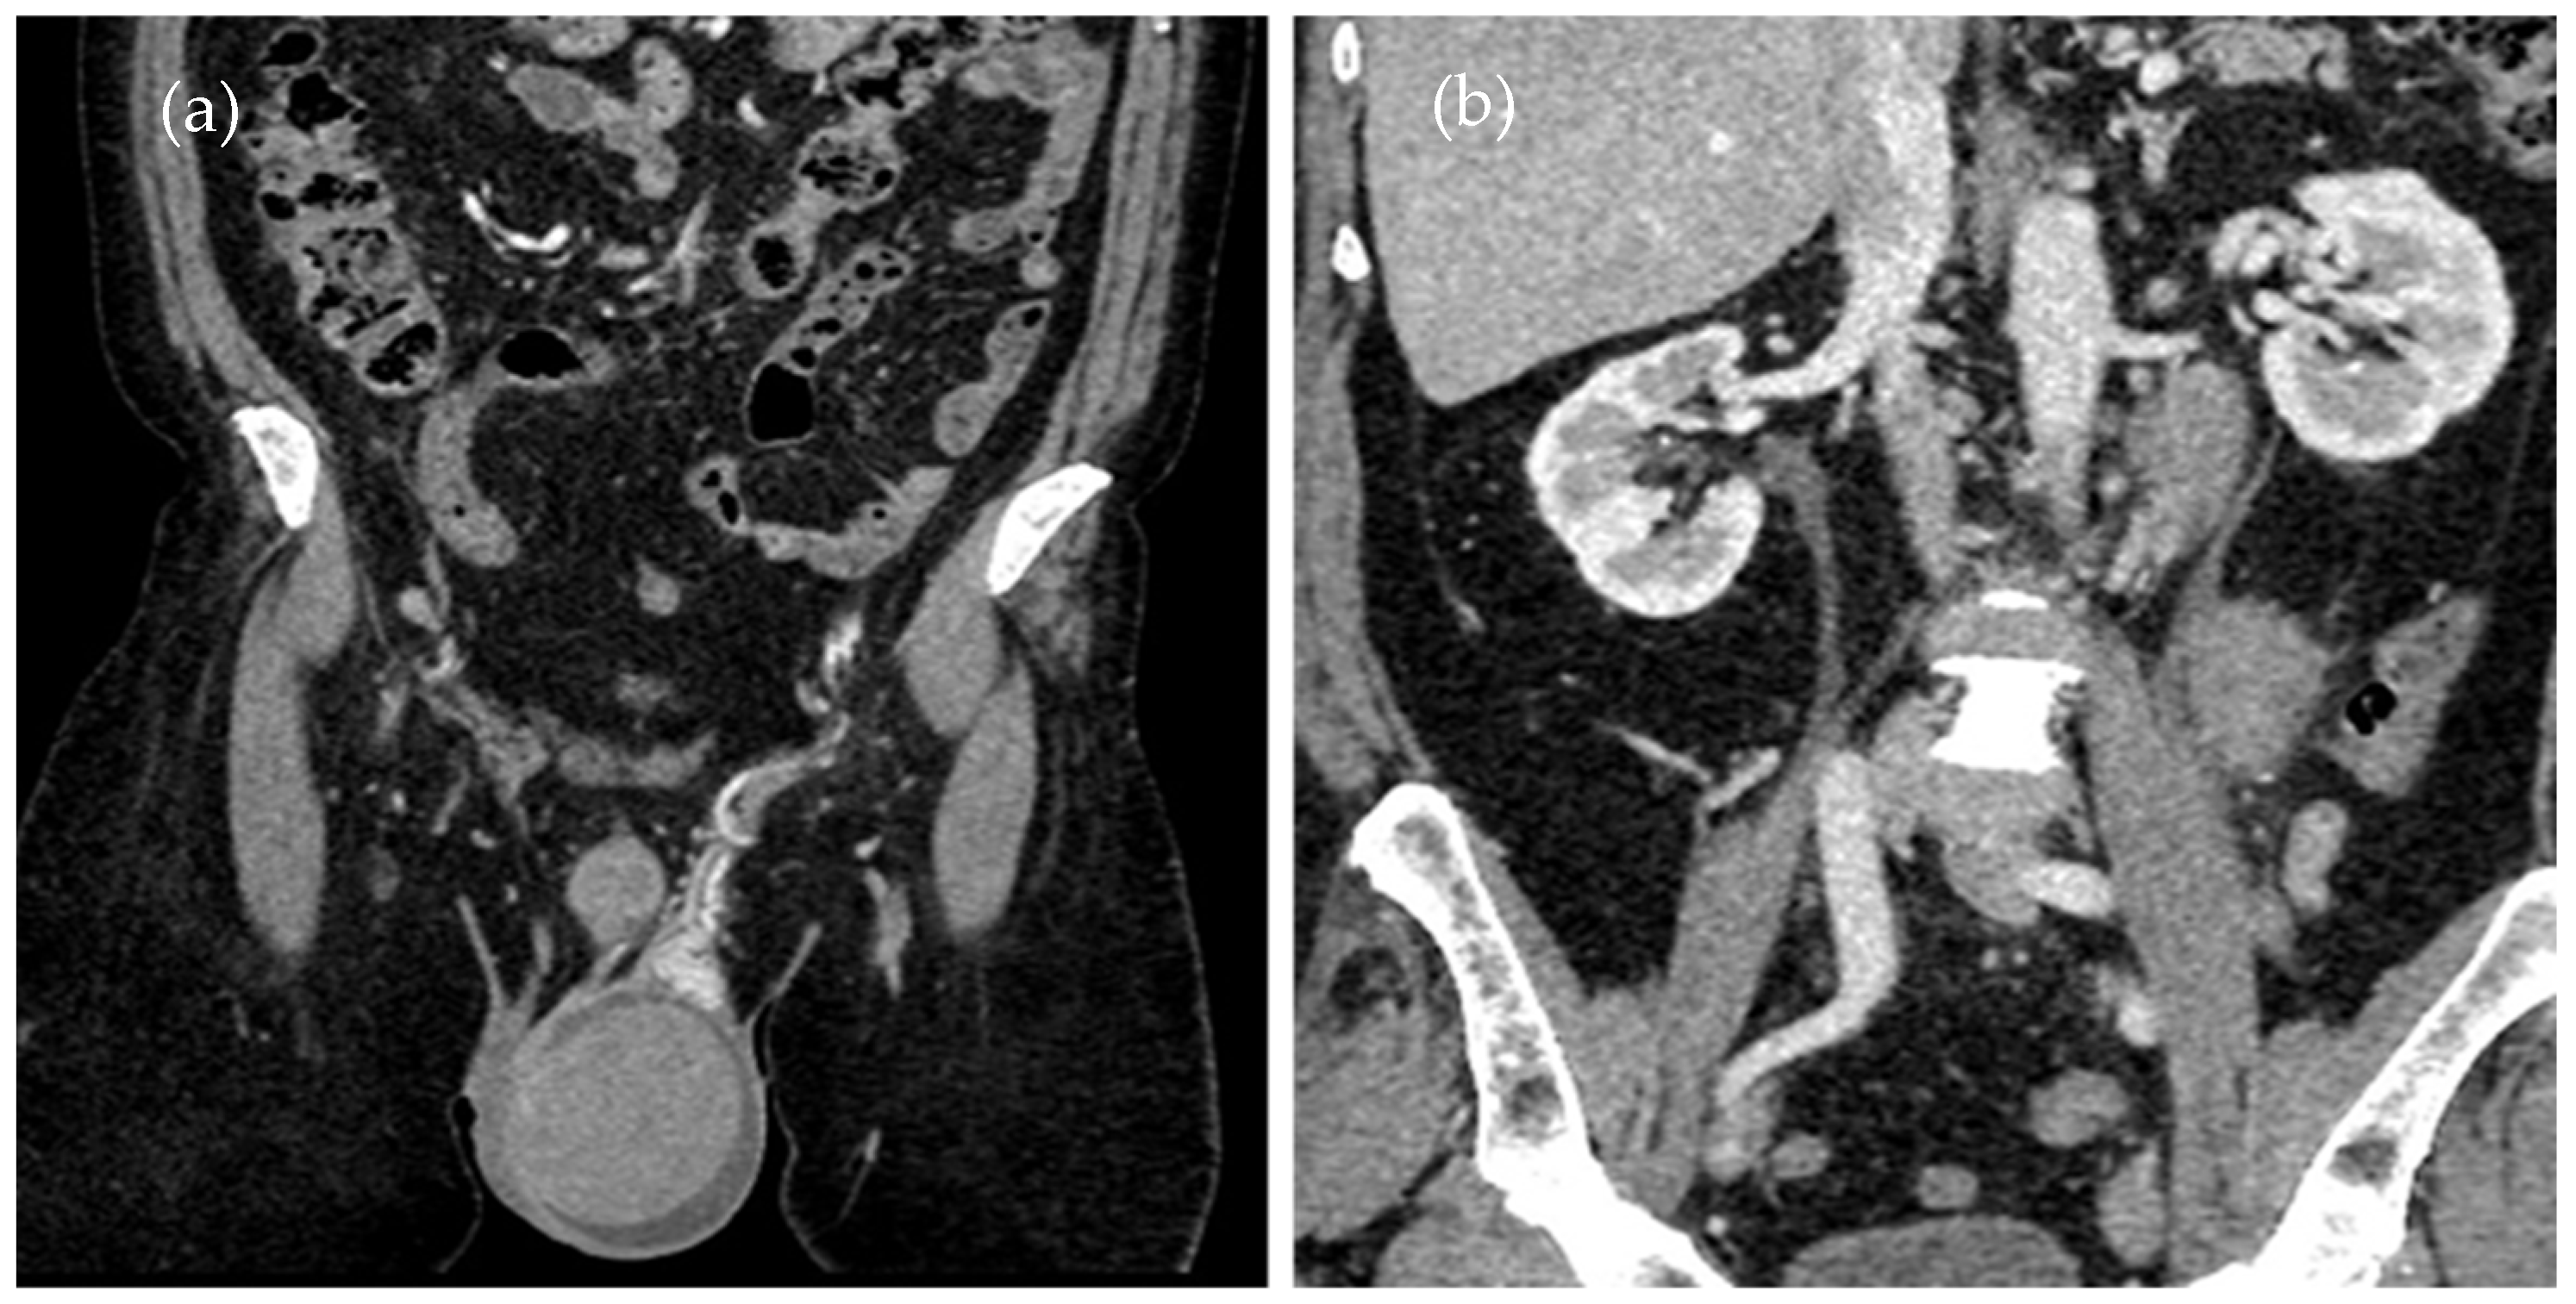

Given the history of ALL and the patient’s symptoms, a monitoring CT scan (Figure 1a,b) was performed to assess any eventual organ relapse.

Figure 1.

This is a figure of abdominal–pelvic contrast-enhanced CT in the coronal plane with (a) an enlarged left testicle and (b) adenopathy on the left testicular vein pathway.

A contrast-enhanced CT scan of the thorax, abdomen, and pelvis was performed, showing an enlarged left testicle (ca. 100/60/60 mm) with increased native densities (Figure 1a), rich peripheral vascularity, discreetly iodophilic in nature, with peri-testicular fluid accumulation and epididymal contrast uptake at the level of the spermatic cord and scrotum on the left, and tissular nodules with heterogeneous iodophilia along the course of the left testicular vein to the level of the left renal hilum, in keeping with adenopathy (42/26/36 mm underlying the left renal hilum, 31/27/54 mm and 13 mm, respectively Figure 1b).